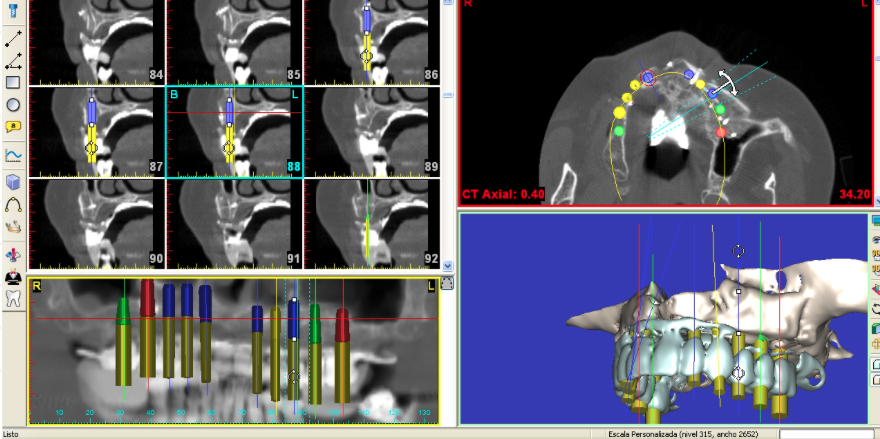

Modelos 3D de planificación

Modelos de planificación 3D para implantes zigomáticos

Modelos 3D de CBCT de esqueleto facial par la planificación de IMPLANTES ZIGOMÁTICOS.

Modelos de planificación 3D para estructuras subperiósticas

Modelos 3D de CBCT de esqueleto facial par la planificación de Estructuras Subperiósticas.